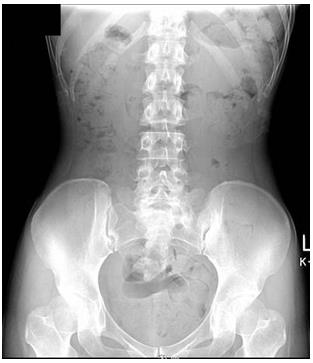

腹部X線檢查(俯臥)

體型偏瘦。大便中有空氣,可推斷糞便停滯。從盲腸到橫結(jié)腸,降結(jié)腸,乙狀結(jié)腸,直腸,以及直腸到結(jié)腸部分都有糞便停滯。診斷宿便過(guò)多。